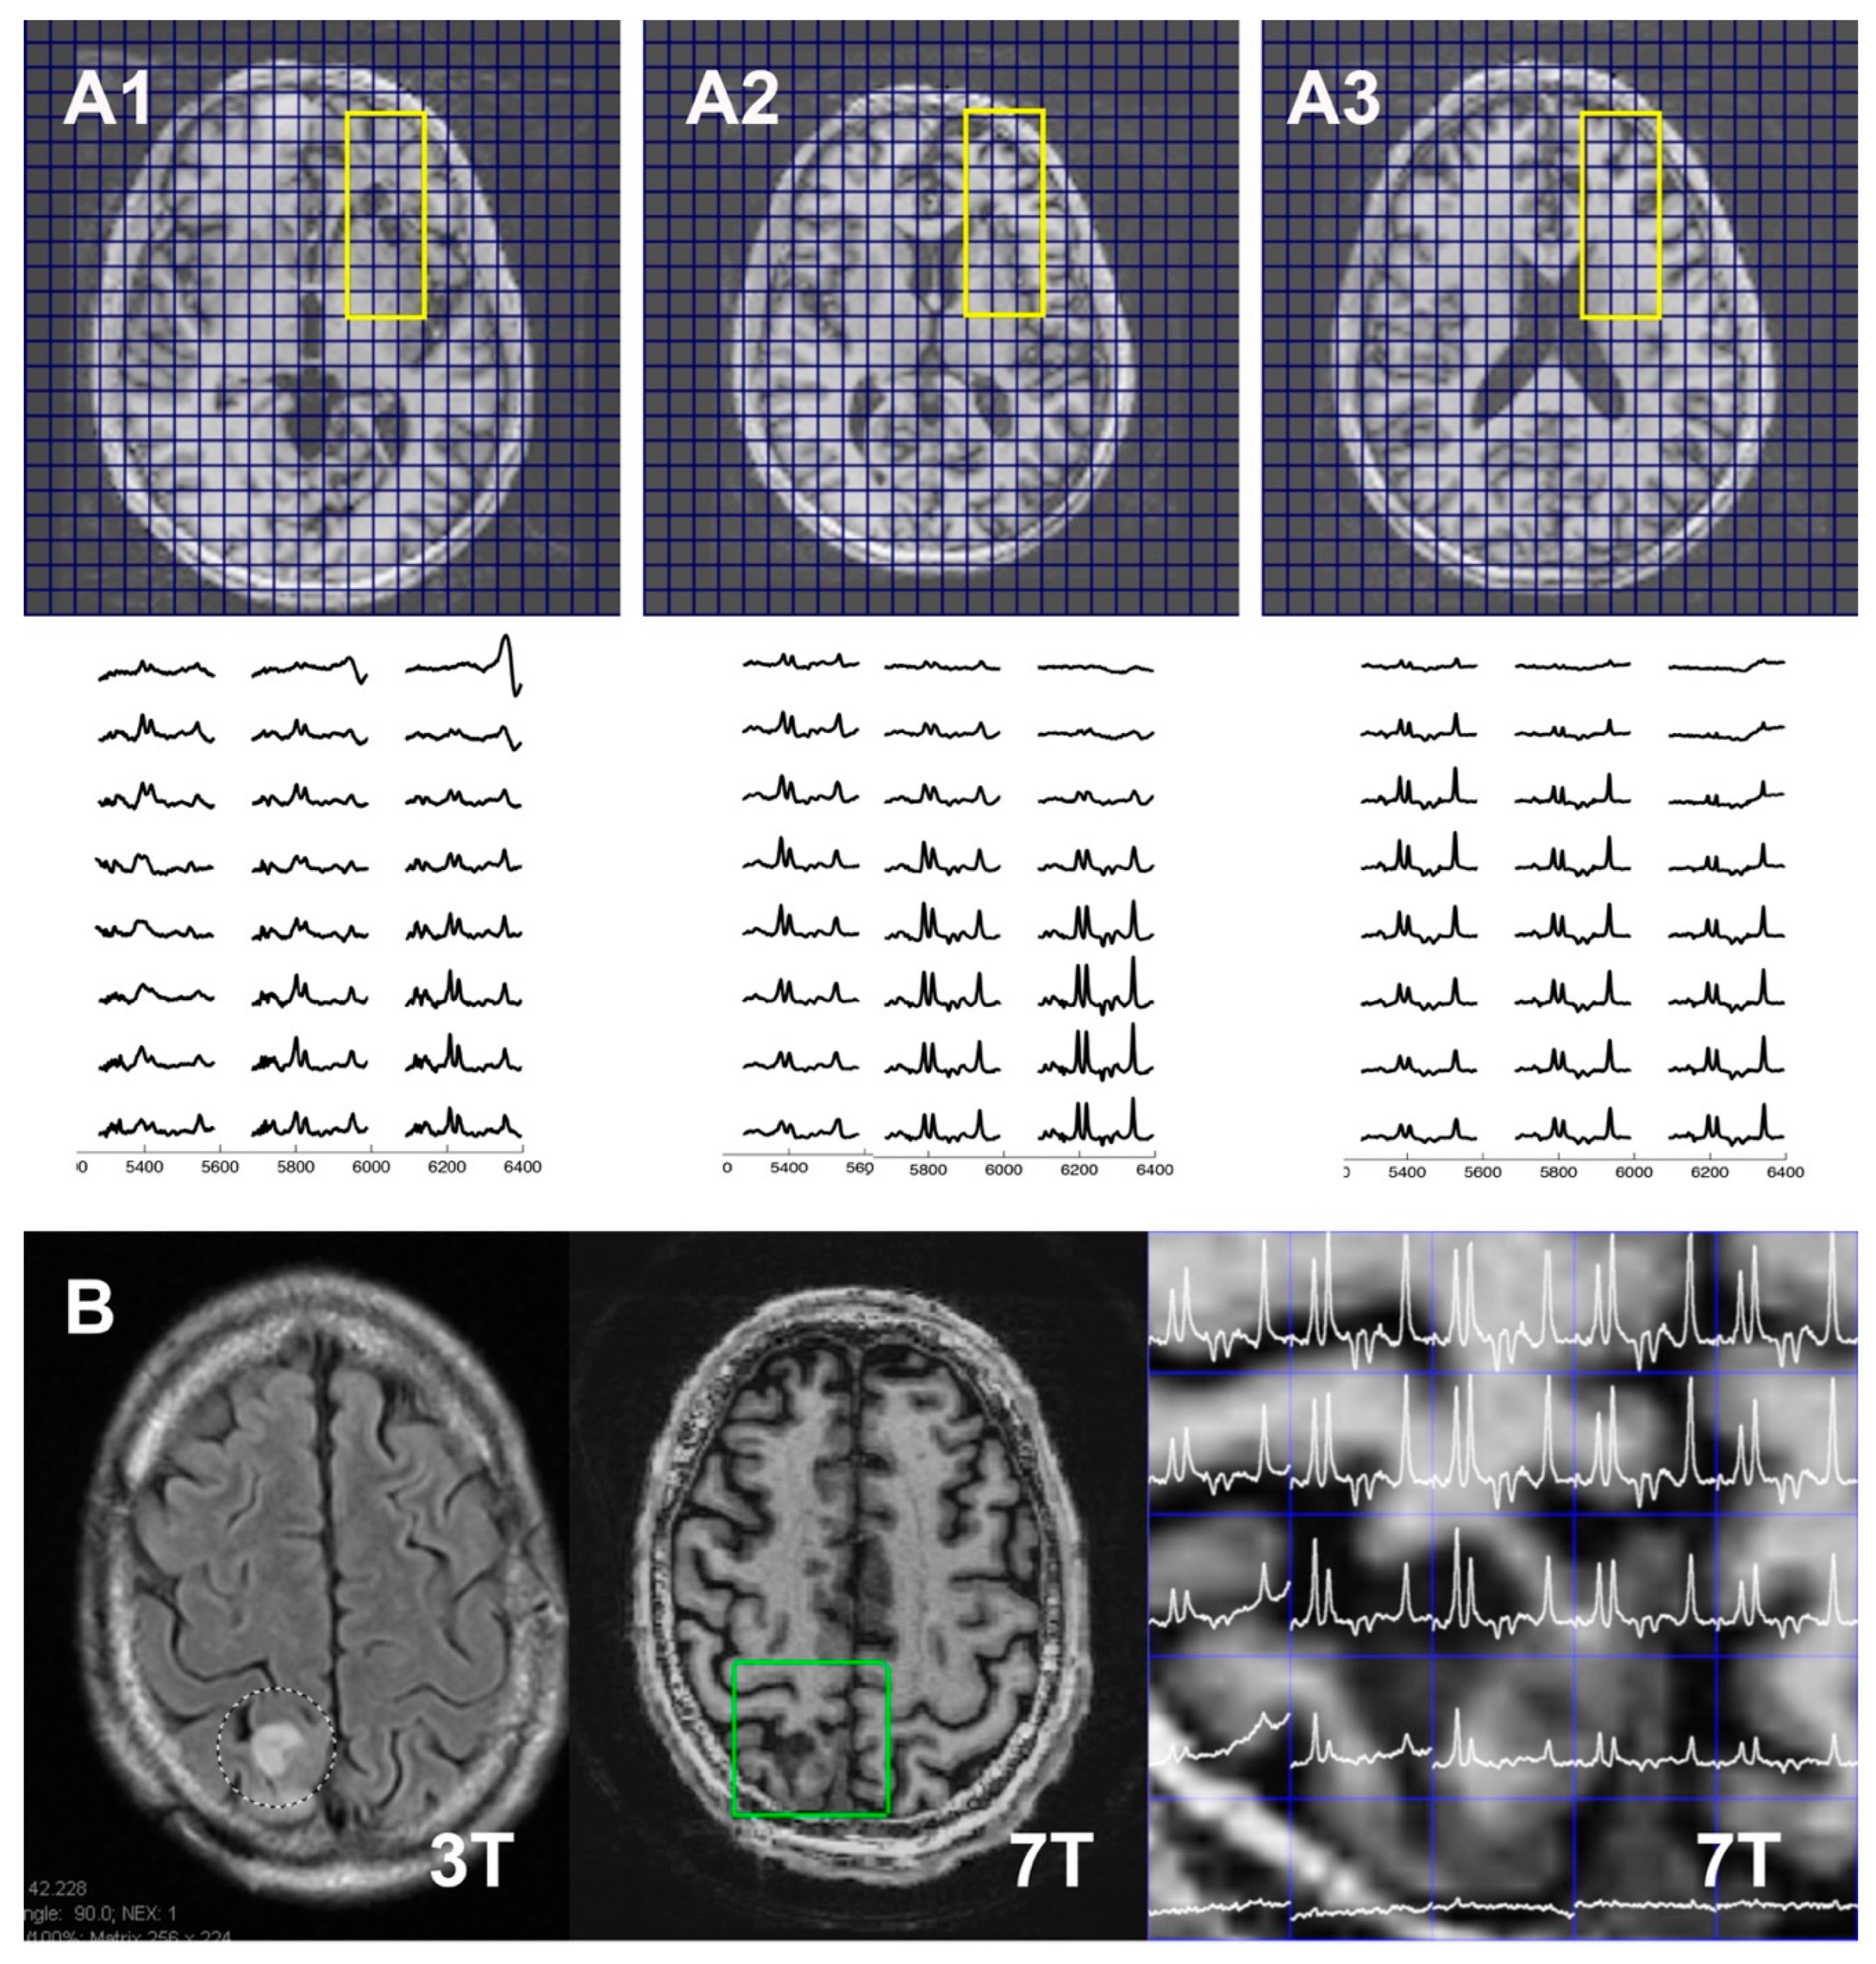

3.3. Application in Tumor Patients